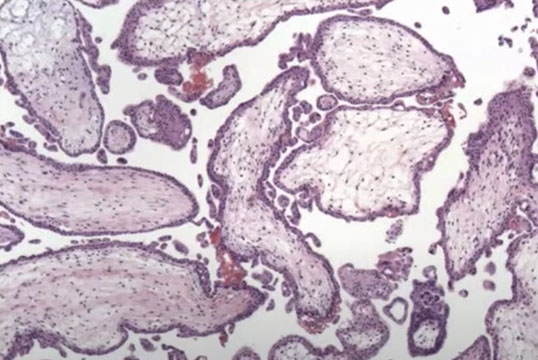

Hydropic Abortus

Presents as missed abortion c declining hCG levels

- grossly tissue scant, fetal parts usually not visible

- villi are uniform, round and occasionally fibrotic

- stromal vessels are rare and nonbranching, can have nRBCs

- trophoblastic hyperplasia is rare, but when present is polar

IHC: (+) p57 villous stromal cells and cytotrophoblasts

Genes: are diploid or aneuploid, occasionally triploid

Px: no inc risk of persistent dz

A and B, Hydropic nonmolar abortions show nuclear p57 staining in villous cytotrophoblast and stromal cells. C, Early complete hydatidiform mole with hypercellular, myxoid stroma, and circumferential trophoblastic proliferation. P57 immunostaining is absent in villous cytotrophoblast and stromal cells (D). Note the internal positive control in decidua in the upper portion of image (hematoxylin-eosin, original magnification x10 [A and C]; p57, original magnification x10 [B and D]).